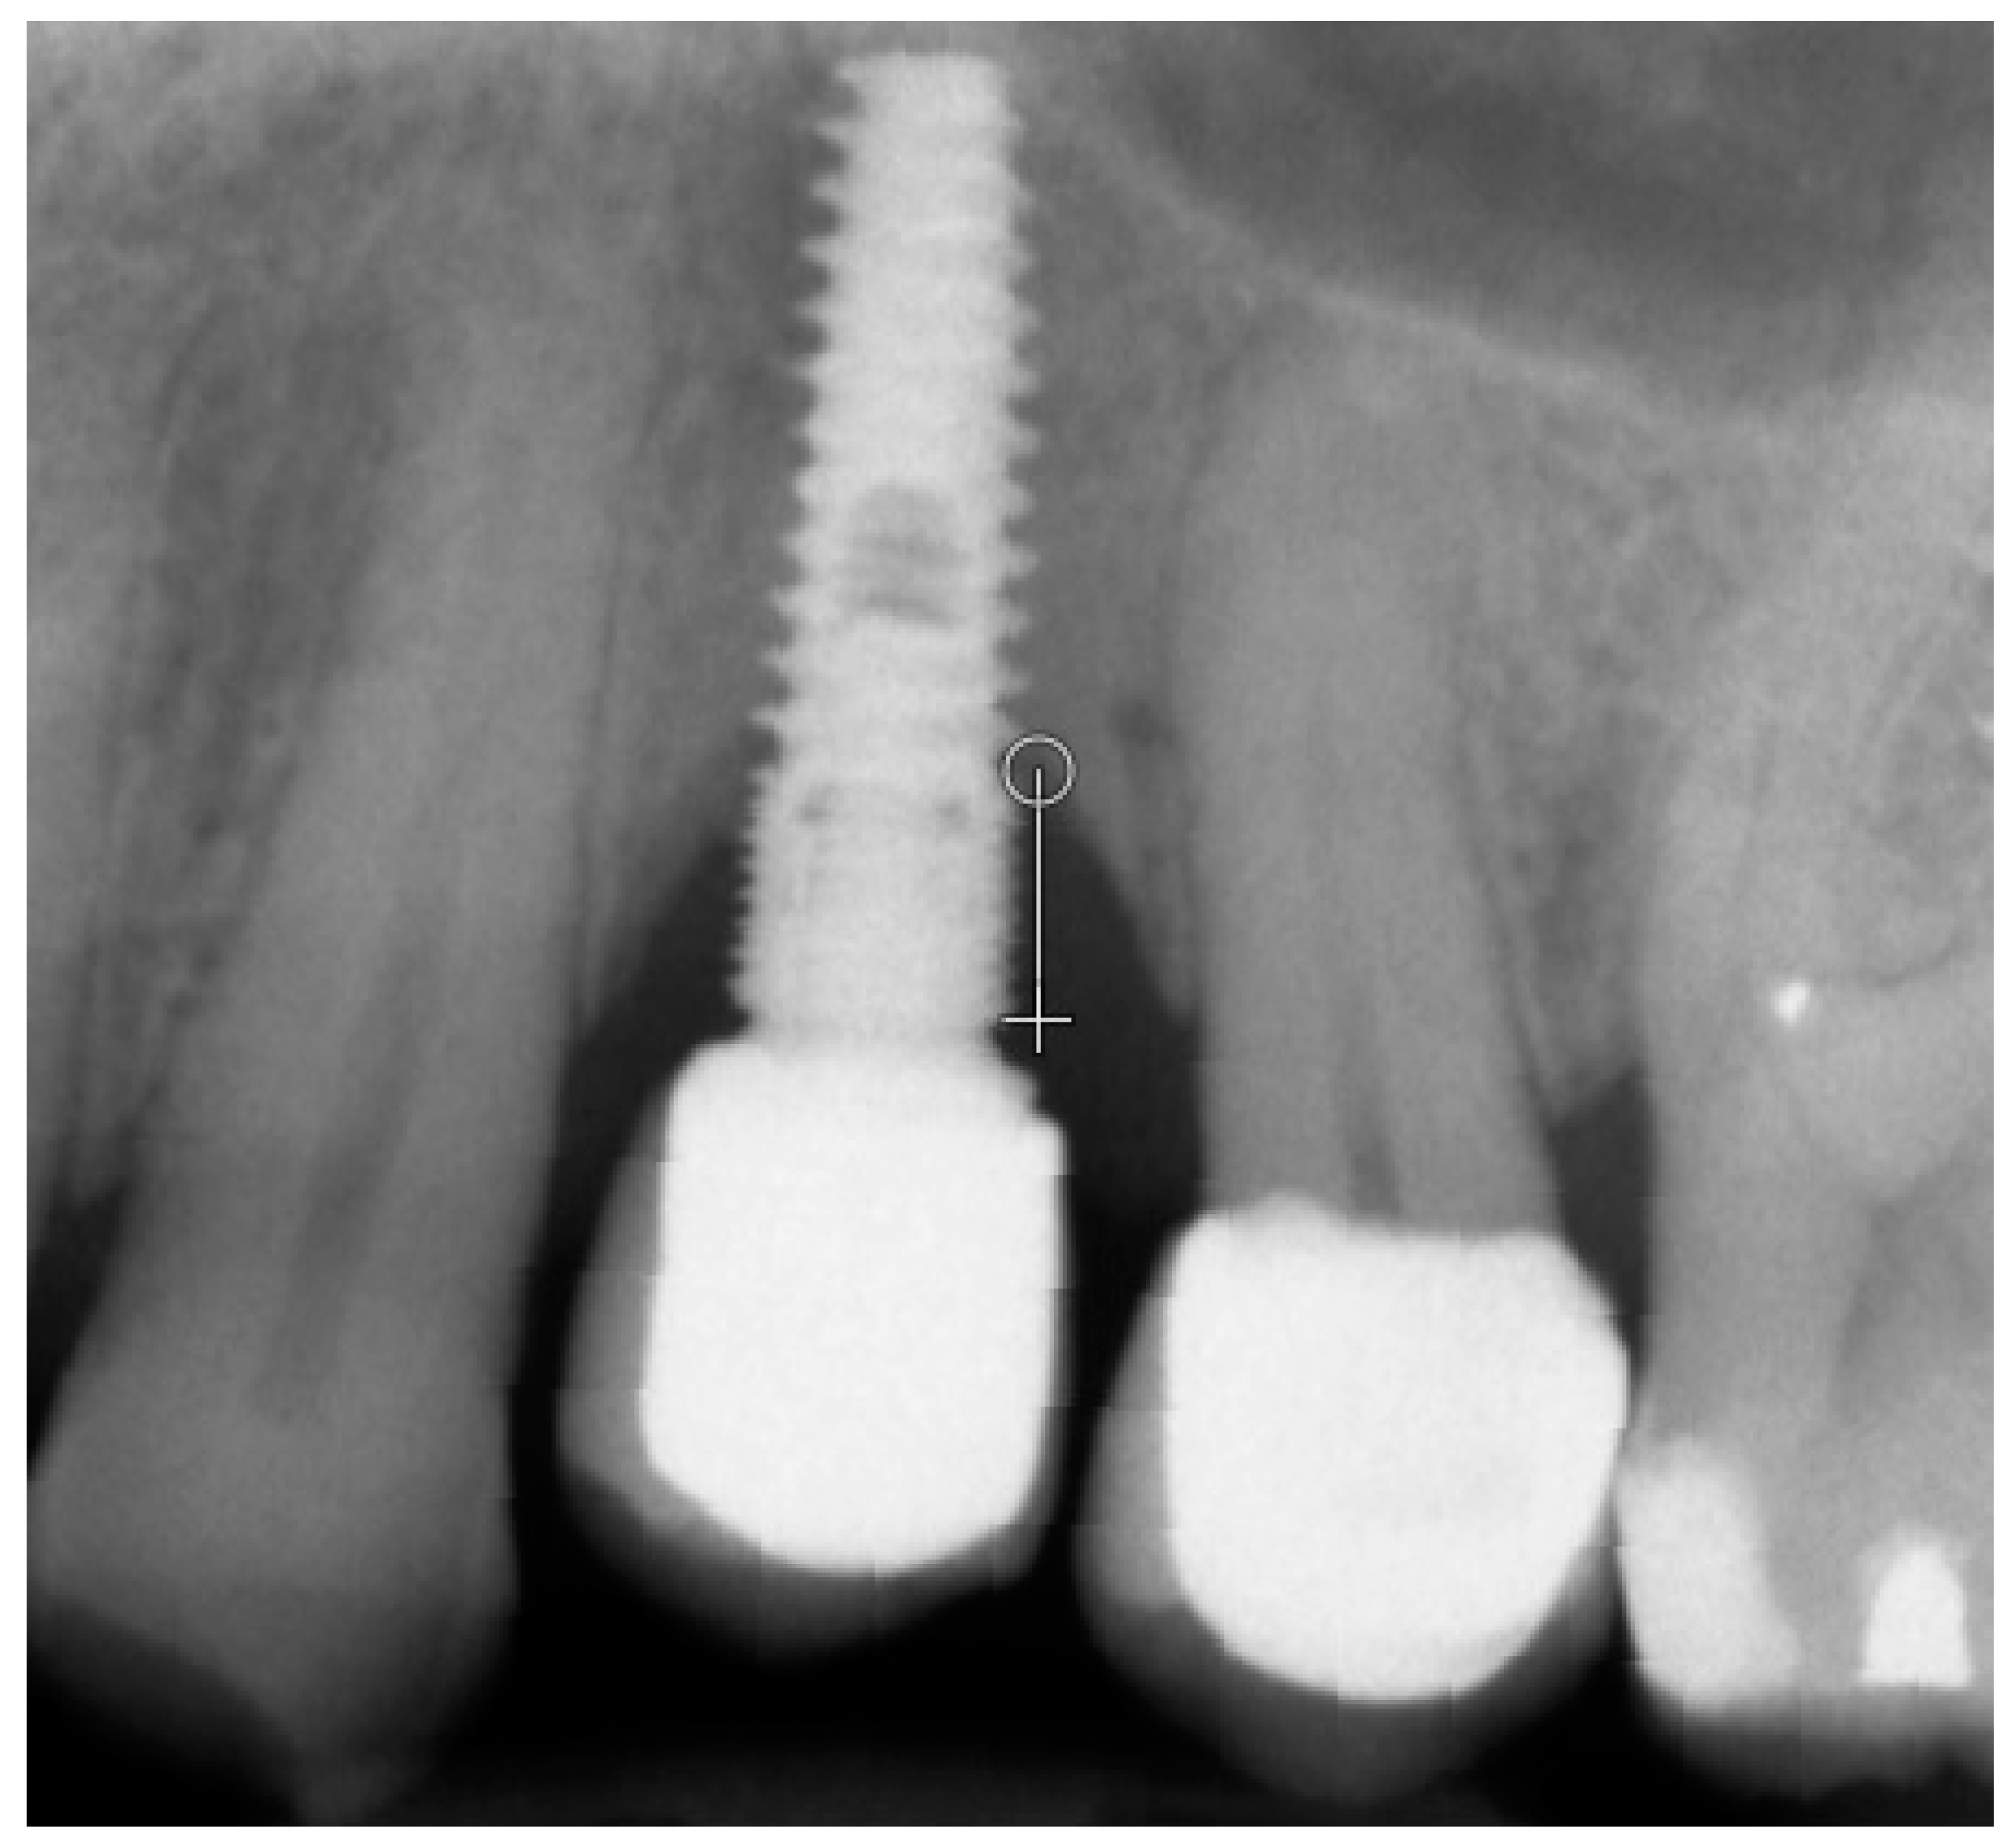

2. Materials and Methods

- Kozakiewicz, M.; Wach, T. Exploring the Importance of Corticalization Occurring in Alveolar Bone Surrounding a Dental Implant. J. Clin. Med. 2022, 11, 7189. [Google Scholar] [CrossRef]

- Kozakiewicz, M.; Skorupska, M.; Wach, T. What Does Bone Corticalization around Dental Implants Mean in Light of Ten Years of Follow-Up? J. Clin. Med. 2022, 11, 3545. [Google Scholar] [CrossRef] [PubMed]

- Kozakiewicz, M. Measures of Corticalization. J. Clin. Med. 2022, 11, 5463. [Google Scholar] [CrossRef]